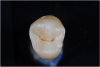

Fig 14. ICDAS code 4: Dark gray shadow visible in dentin in indicated area.

Figure 14

Next, regardless of chalkiness, the clinician examines the dry grooves for the presence of any areas of localized enamel breakdown, or microcavitations, which represents ICDAS code 3 lesions (Figure 12 and Figure 13). Additionally, the presence of an underlying shadow, which indicates dentin caries showing through, is considered an ICDAS code 4 lesion (Figure 14). Either or both of these findings results in a classification of the tooth structure as CCS code 2 moderate.